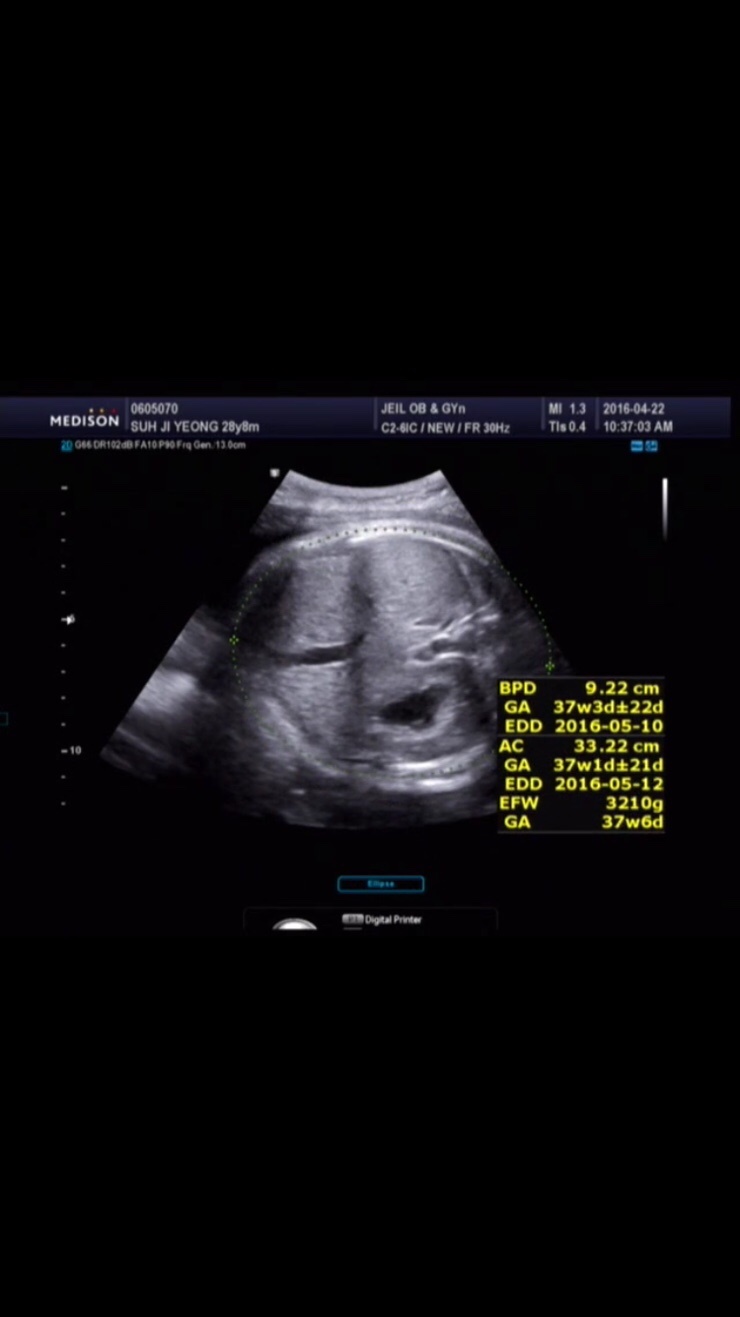

4월 30일 7:40m열매 만나다 유도분만 - 자연분만 3.2kg 40주+2...